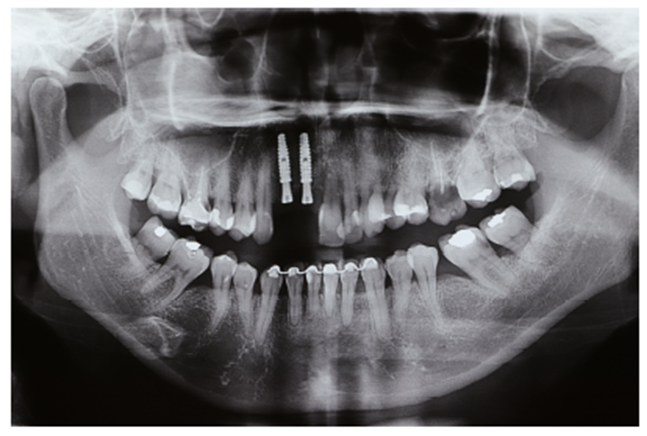

Após 4 meses, foi realizada radiografia panorâmica para o momento de abertura dos implantes (Figura 20). Foi planejado e escolhido os munhões da linha Smart Implacil (3.3x4x2.5) e confeccionadas duas coroas metalocerâmicas do tipo parafusada, visando maior possibilidade de reversibilidade e manutenção (Figuras 21 e 22).